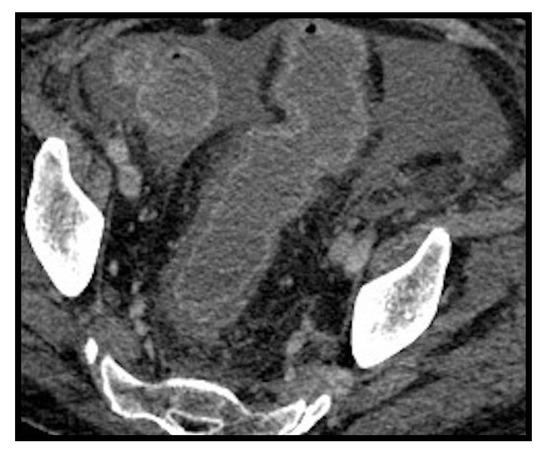

Figure 13. Pancreatitis. Enlarged and edematous pancreas especially at the head, with fat stranding and peripancreatic fluid collection extending along the left anterior pararenal space.

Because of the expression of ACE-2 receptors also in pancreatic cells, pancreatitis can occur in COVID-19 patients [46,47,48] (Figure 13). Funt et al. [47] investigated the presentation rate of pancreatitis in COVID-19 patients examined with CT, which amounted to 1.5%. They searched for the most common causes of abdominal pain in two groups of patients: COVID-19 positive and COVID-19 negative, respectively. In the subset of acute disease, they documented: inflamed bowel, pancreatitis, pyelonephritis or cystitis more frequently in COVID-19+ patients rather than in COVID-19- patients. As illustrated by Wang et al. [56], pancreatitis presents in COVID-19 with a variable percentage ranging from 1–2% of mild cases to 17% of severe cases. Bozdag A. et al. [57] argue that in the literature the pancreatitis diagnosis was based only on amylase and lipase elevation, while the radiological findings were described only in case reports. In one case report necrotizing pancreatitis was described [58].